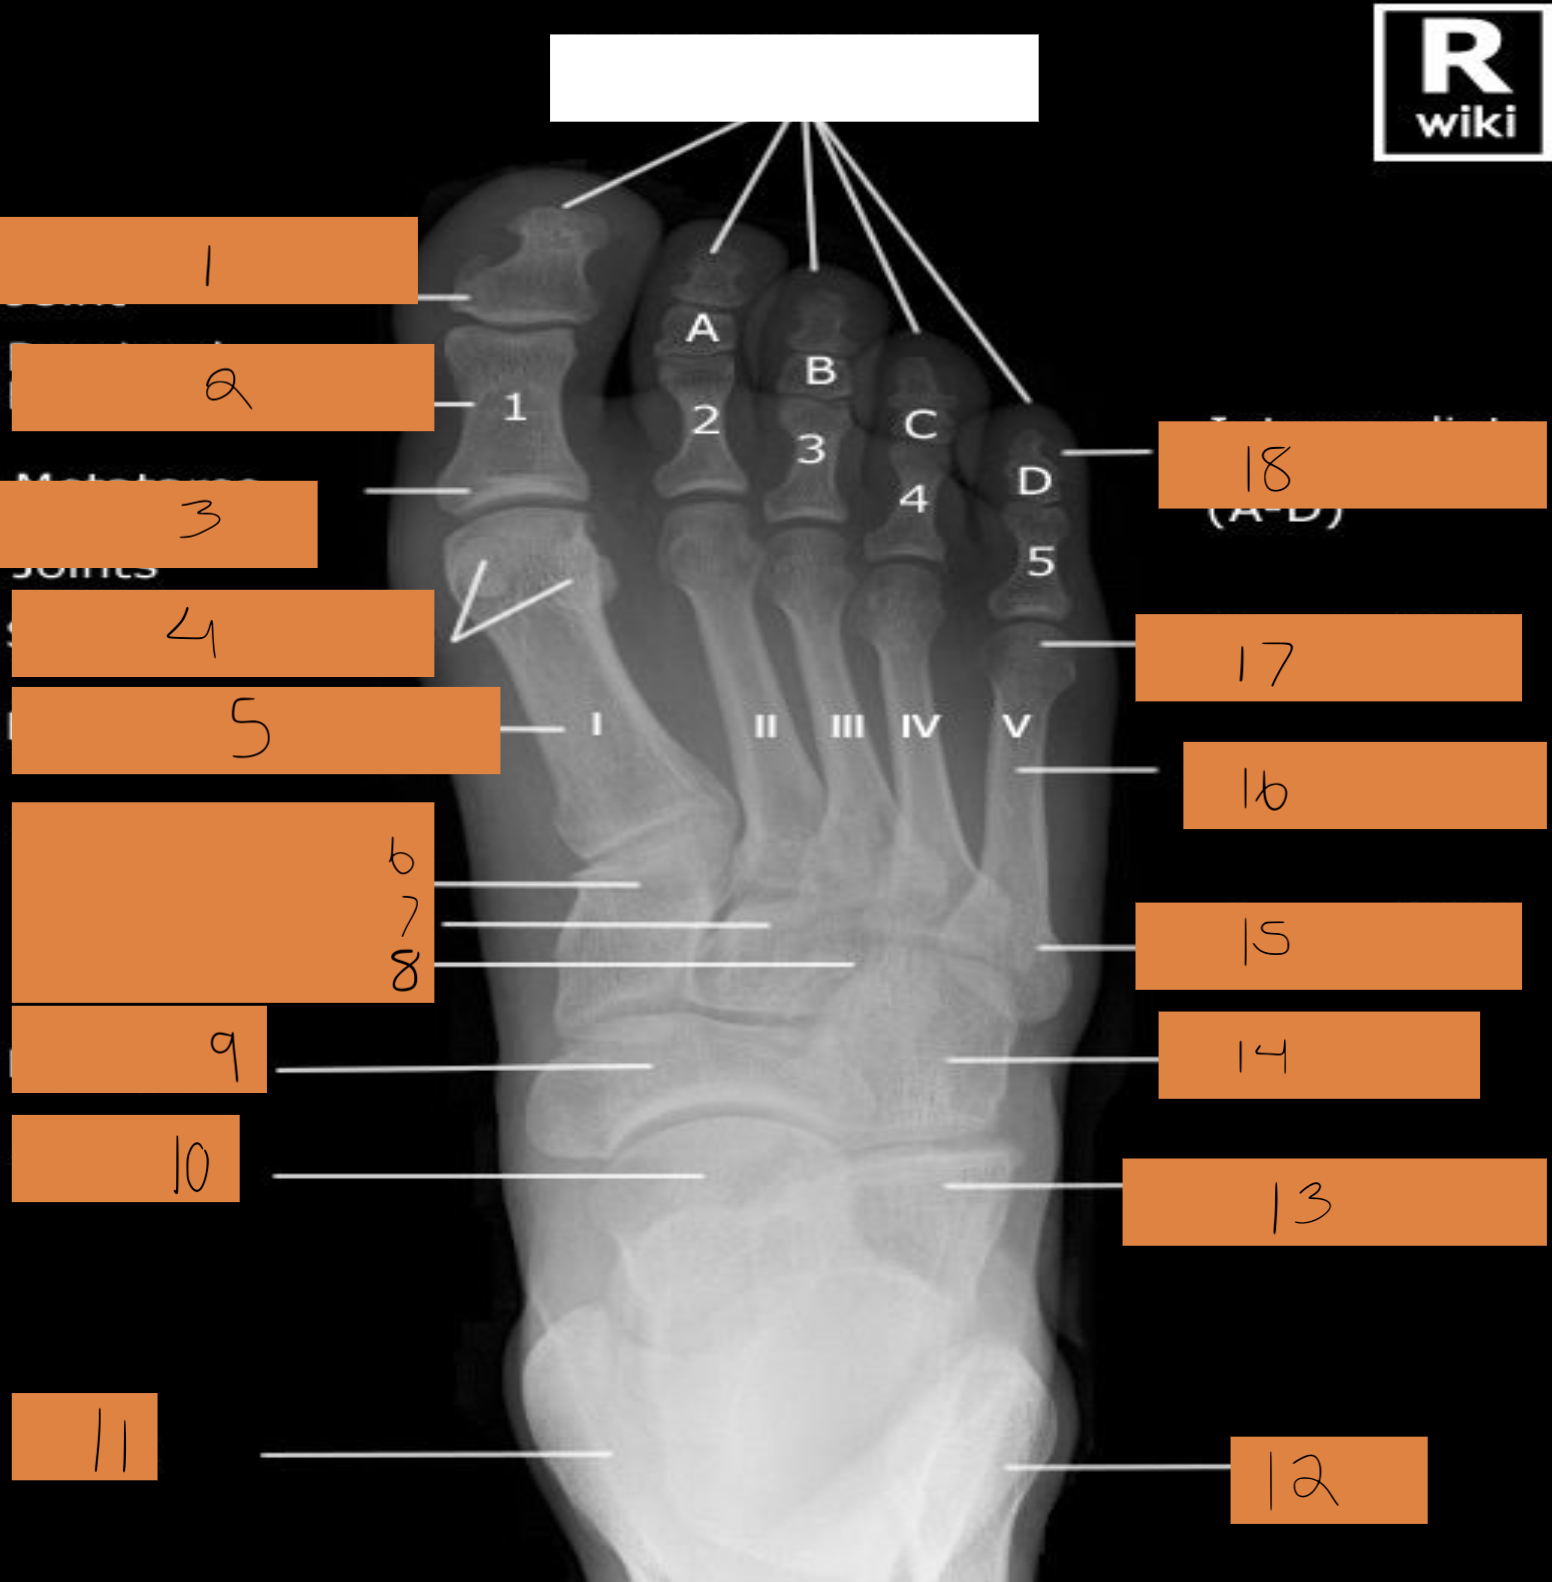

1

distal phalanx

2

middle phalanx

3

proximal. phalanx

4

sesamoid bones

5

metatarsals

6

cuneiforms

7

cuboid

8

navicular